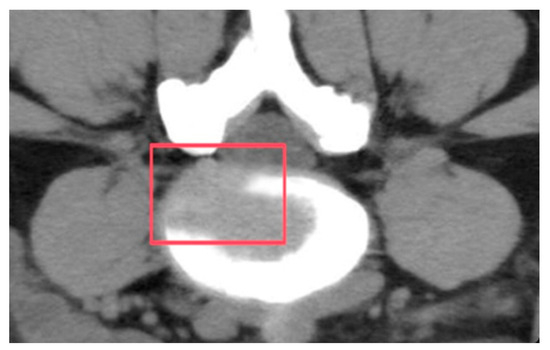

Chronic low back pain (CLBP) affects up to 58% of the population [1] and is primarily caused by intervertebral disc degeneration (IVDD). Stress imbalance and water loss weaken the intervertebral disc (IVD) [2,3]. This degeneration frequently occurs at the crucial load-bearing region of the lumbar L4–L5 segment (Figure 1), studies have found that in patients with chronic low back pain, L4–L5 segments are the most common site of degenerative disc disease, and L4–L5 is located in the lumbo–sacral transition area, which carries the redistribution of upper body weight and axial pressure, and daily activities (such as sitting and bending) can create constant stress here. High-impact exercise (such as weightlifting) further increases the mechanical stress of this segment through shear and rotational forces, leading to microdamage and an accelerated degeneration of the annulus [4].

Figure 1. Location of the L4–L5 lumbar vertebrae in the human body.